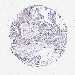

OVARIAN CANCER - Protein expressioni

A mouse-over function shows sample information and annotation data. Click on an image to view it in a full screen mode. Samples can be filtered based on level of antibody staining by selecting one or several of the following categories: high, medium, low and not detected. The assay and annotation is described here.

Note that samples used for immunohistochemistry by the Human Protein Atlas do not correspond to samples in the TCGA dataset.

Antibody stainingi

Antibody staining in the annotated cell types in the current human tissue is reported as not detected, low, medium, or high, based on conventional immunohistochemistry profiling in selected tissues. This score is based on the combination of the staining intensity and fraction of stained cells.

Each image is clickable and will lead to virtual microscopy that enables deeper exploration of all samples and also displays staining intensity scores, fraction scores and subcellular localization as well as patient and tissue information for each sample.

Antibody HPA048677

Staining

High

Medium

Low

Not detected

Intensity

Strong

Moderate

Weak

Negative

Quantity

>75%

75%-25%

<25%

None

Location

Nuclear

Cytoplasmic/membranous

Cytoplasmic/membranous,nuclear

Cystadenocarcinoma, serous, NOS